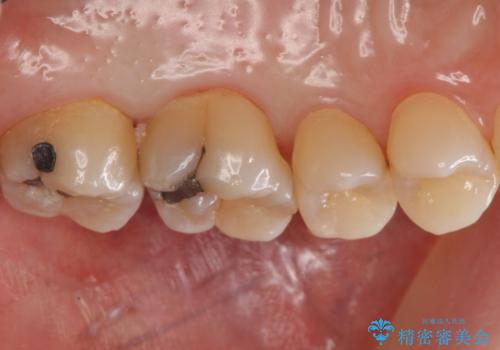

奥歯の虫歯 セラミックインレーによる治療

- 定期検診にて来院、症状はないものの右上の奥歯に虫歯が再発していました。

視診・レントゲン画像より虫歯の大きさを判断し、虫歯の除去後セラミックインレーにて修復することになりました。